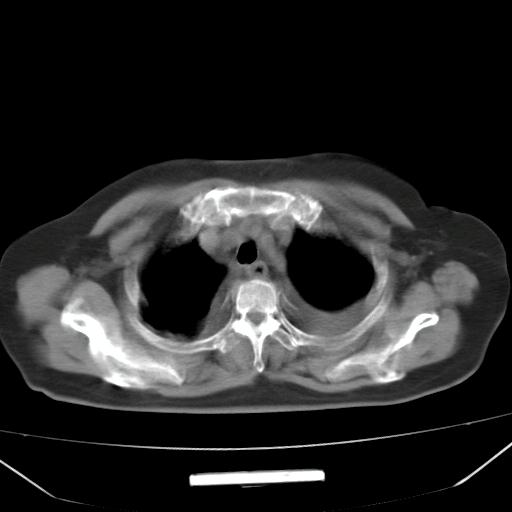

以下是引用liuyue在2008-4-19 22:25:00的发言:[br]先考虑:1.心衰伴肺水肿、双侧胸腔积液、叶间积液、双下肺不完全性肺不张; [br] 2.冠状动脉粥样硬化。

以下是引用lijuanln在2008-4-19 23:05:00的发言:[br]两侧胸腔积液,肺水肿[br]心包积液[br]提示心衰

以下是引用jiangjing在2008-4-20 10:43:00的发言:[br]结合病史支持 冠心病[冠状动脉钙化],心功能不全,肺淤血、肺水肿,双侧胸腔与斜裂积液